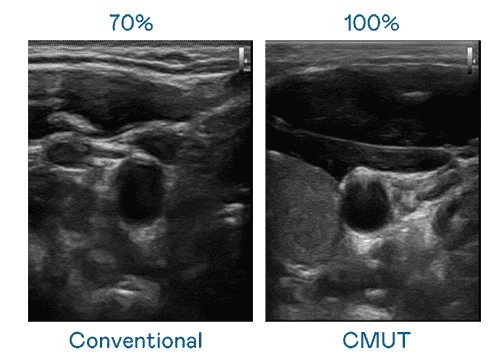

CMUT 技术是一种用电容式微机电元件来产生超音波讯号的技术。。与传统 PZT 压电式技术相比,,,CMUT 频宽增加 30%,,,,更宽频的超音波讯号让影像解析度大幅提升,,,是实现高影像品质医疗超音波扫描、、、促进精准医疗发展的关键技术。。

超音波影像的解析度高低,,,,首先取决于探头能发出的讯号频宽。。。冰球突破 CMUT 可提供高清晰的超音波讯号,,提供高频宽、、、高灵敏度、、、、影像纹理细节更高的超音波影像,,,,协助医护人员缩短影像判读时间及利用精准的医疗影像进行诊断。。。